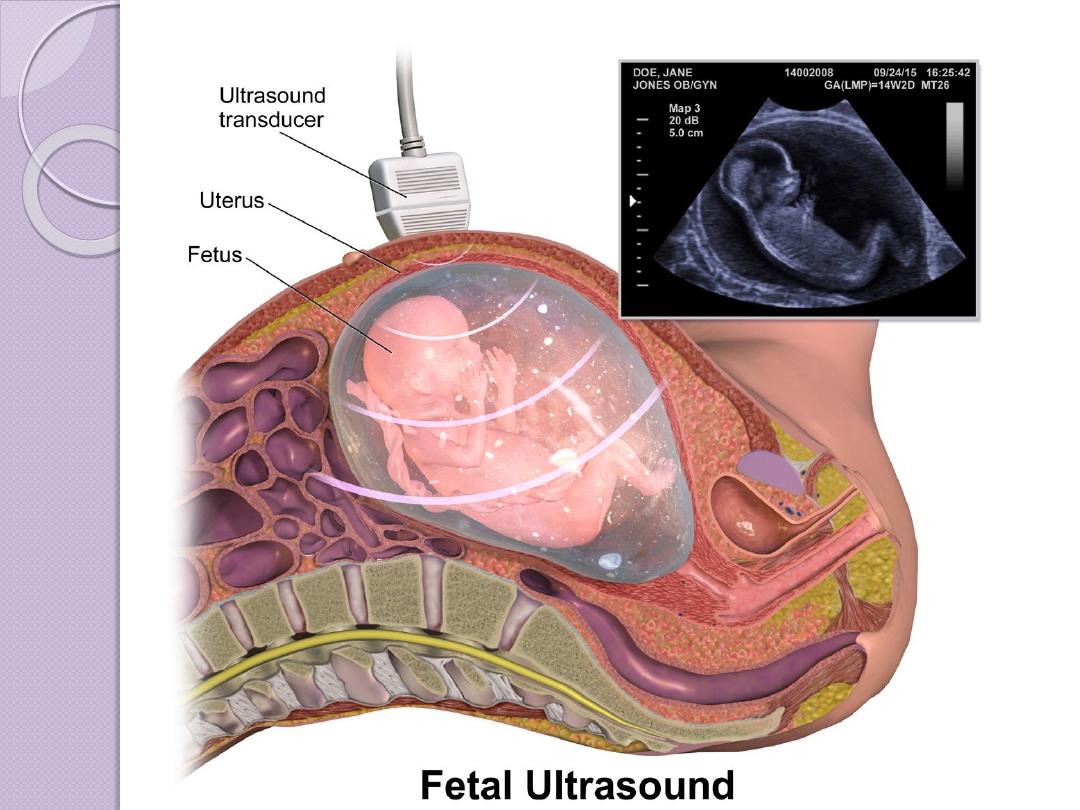

Ultrasound

Ultrasonography is made up of longitudinal waves of

frequency greater than 20,000 Hz

Pulsed ultrasonographic imaging sends an ultrasonic pulse

into the body and measures the time of echo return, which is

related to the distance to the reflecting surface.

Transducer is the main sonographic machine part which

made from a material which can change the electrical waves

to longitudinal sonographic waves (the range which is used

from 3 mega HZ which is used in general abdominal US to

10-12 MHZ) in superficial organs like ophthalmic

examination )

The reflection of the tissue interfaces are received again by

transducer and according to the amount of echoes received

the tissue brightness will be different from tissue to a tissue